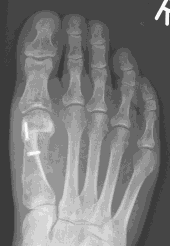

This is an osteotomy in the metatarsal head (transposition), the metatarsal head is moved to correct the deformity and fixated with a single screw. It is indicated for mild to moderate deformities. The choice to carry out a Scarf or a capital osteotomy will be made by your consultant.

Scarf osteotomy

This is a transposition osteotomy. It is normally indicated for mild to moderate deformities. The new position of the first metatarsal is maintained with two screws which enables stability.